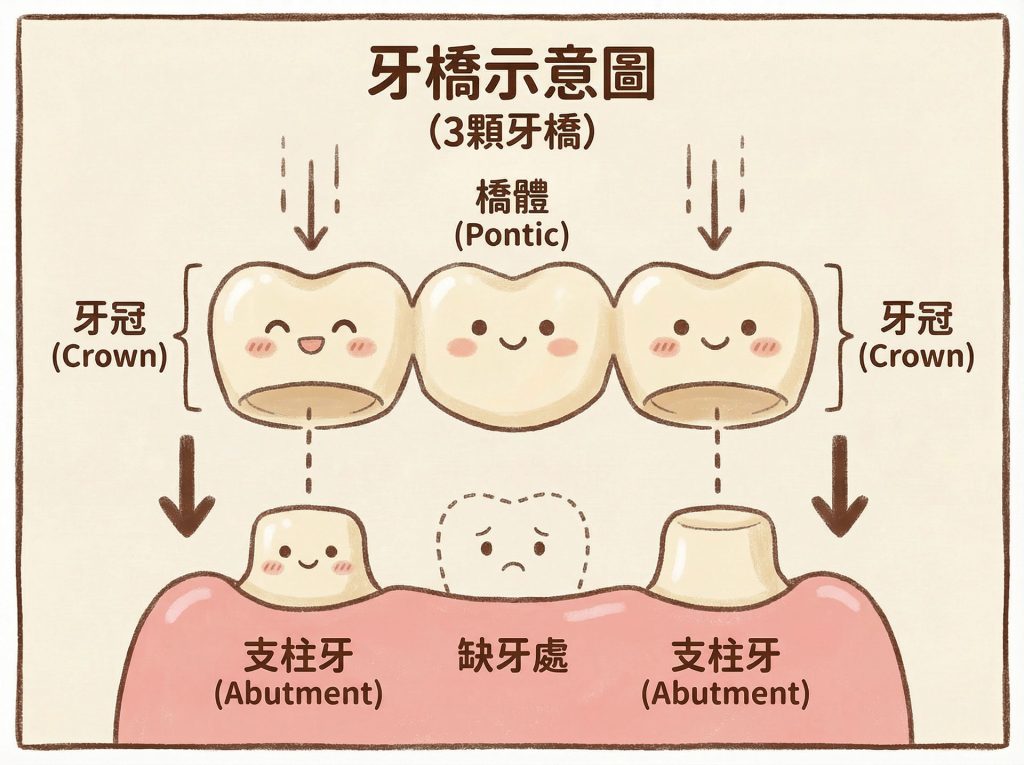

2. 鄰牙本身健不健康,決定了這座「橋」該不該搭

很多人會把焦點放在「中間少了一顆牙」,

但臨床上真正需要一起評估的,往往是缺牙兩側的鄰牙狀況。

牙橋有點像搭橋:中間缺牙的位置是橋面,前後兩顆牙則像橋墩。

橋墩本來就老舊、破損需要補強,把它們一起納入設計,未必是壞事

但如果兩個橋墩本來都穩穩當當、結構完整,卻為了補中間一塊空缺,反而把兩側也削掉一部分來搭橋,那這個代價就要更仔細思考。

所以在評估牙橋時,我不會只看「缺了哪一顆」,而是會進一步看:

前後兩顆牙,是本來就需要保護,還是本來就值得盡量保留?

簡單來說,牙橋不是不能做,關鍵在於前後兩顆牙值不值得一起被納入設計。